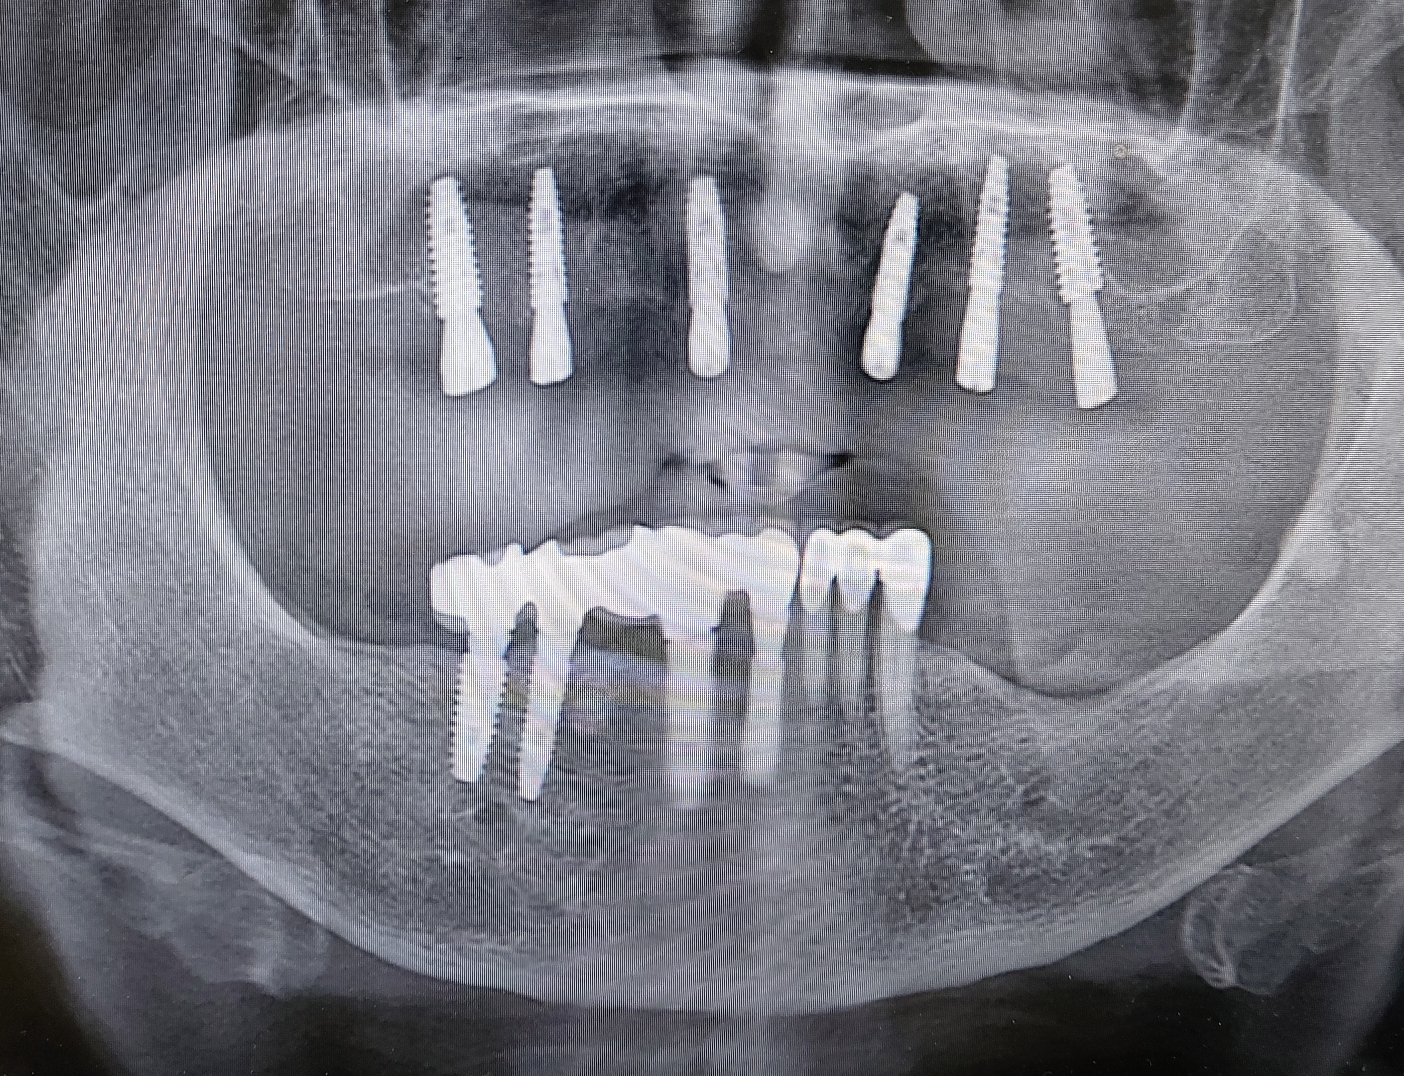

4. 임플란트를 이용한 고정성 보철물

이 방법은 양측 이공 사이에 5개 전후를 심은뒤

최후방 임플란트로 부터 후방 약 15 mm 까지 보철물을 만들어서 완전한 고정성 보철물로 만들어 드리는 방법입니다.

기존에 부분틀니를 사용하셨거나 아니면 무치악 상태의 틀니를 사용했던 환자분들이라면 아주 만족도가 높은 치료 입니다. 단점이 있다면 최후방 임플란트로부터 약 15mm만 연장이 가능하기에 보통 제1대구치 까지만 제작이 됩니다.